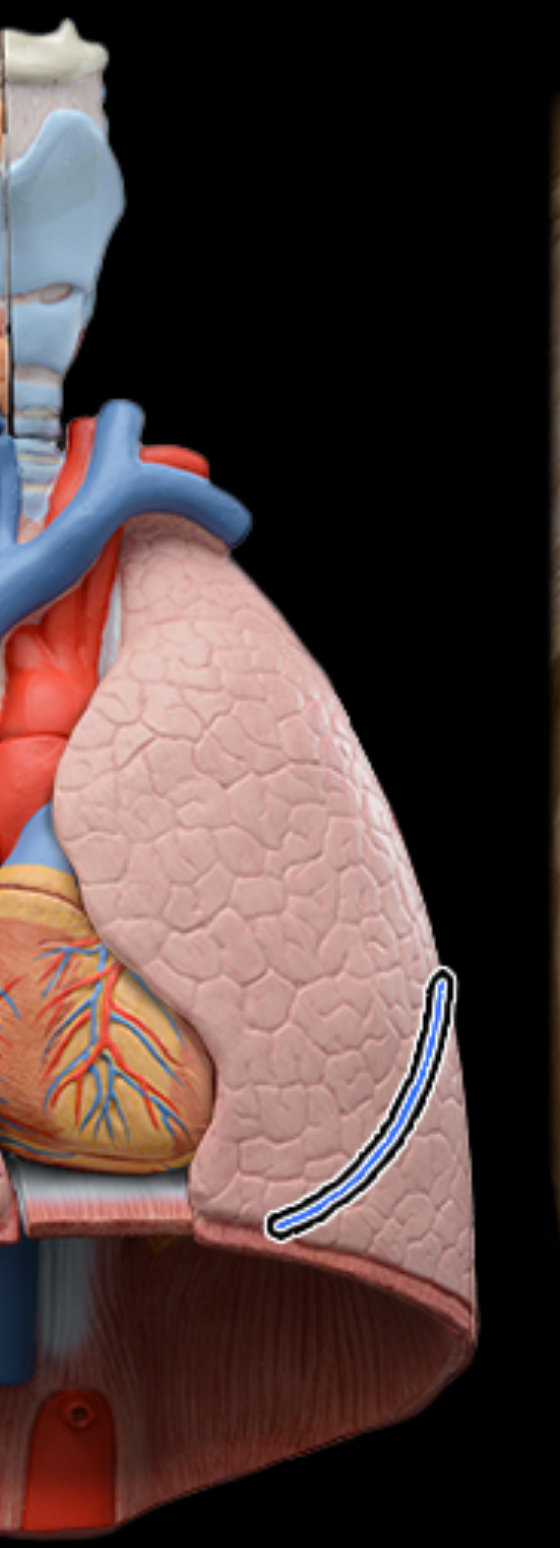

Superior, lobe of right lung

middle lobe of right lung

inferior lobe of right lung

Horizontal fissures of right lung

oblique fissures of right lung

Superior lobe of left lung

inferior lobe of left lung

oblique fissure of left lung

cardiac notch